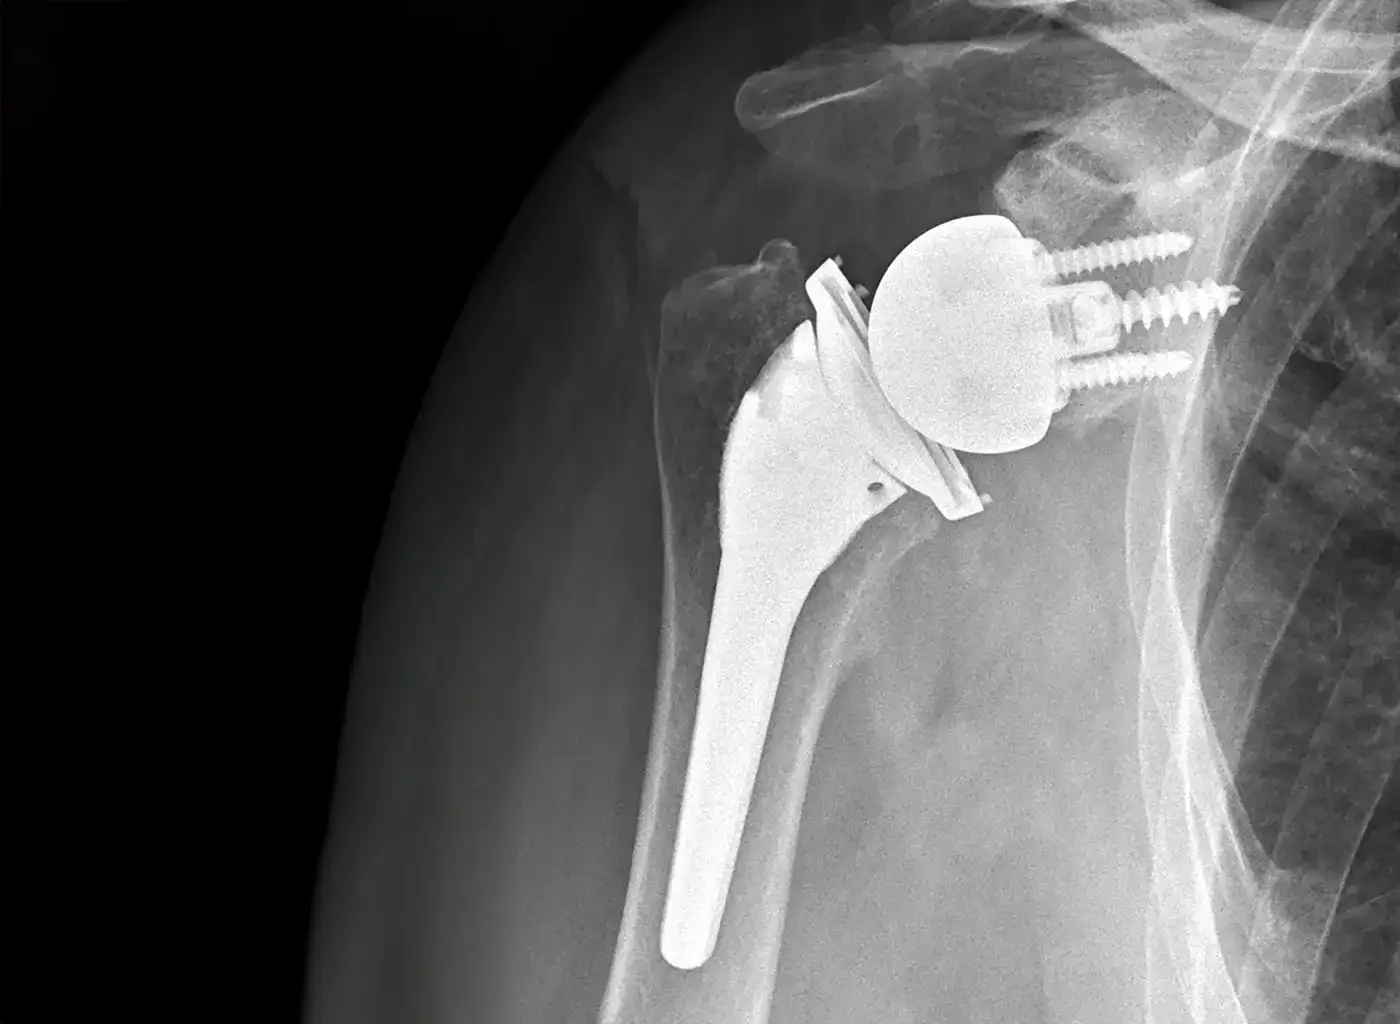

Reverse shoulder replacement, or reverse total shoulder arthroplasty, fundamentally changes this anatomy by “reversing” the position of the ball and socket. The surgeon attaches a metal ball to the shoulder blade (glenoid) and a plastic socket to the top of the humerus. This innovative design changes the biomechanics of the shoulder and allows the deltoid muscle, which covers the shoulder, to take over the function of the damaged rotator cuff. This shift in mechanics may restore movement and relieve pain, even when the rotator cuff is severely compromised.